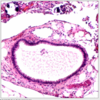

Gross appearance of endosalpingosis?

prominent cyst formation